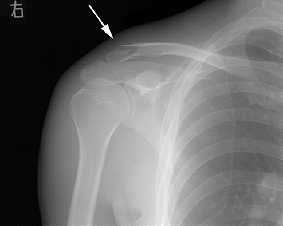

気を取り直して翌8日夜、いぬふぐり・接骨飯塚(カオス飯塚と区別する為の通称)ことDr.飯塚

の当直する某整形外科病院に潜入、特別診察を受ける。その結果骨のズレが少なく靱帯の損傷も無

い模様なので手術必要無し、ベルトに加えテーピングでしっかり固定しておけば更に安心というこ

とだった。上から体重をかけられて悲鳴をこらえて3本のテープ。「問題はツアー中のテーピング

矢印が骨折箇所

テーピングでズレを押さえた状態